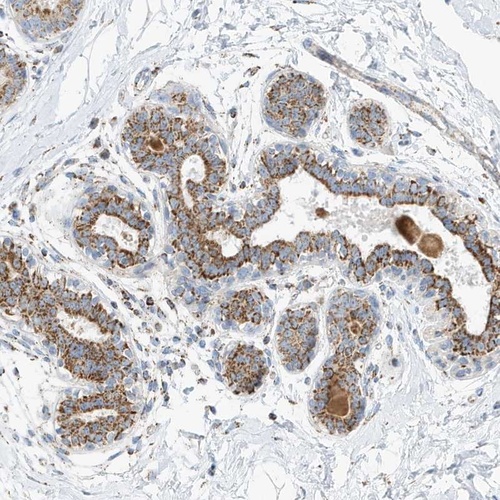

Immunohistochemical staining of human breast shows strong cytoplasmic positivity in granular pattern in glandular cells.